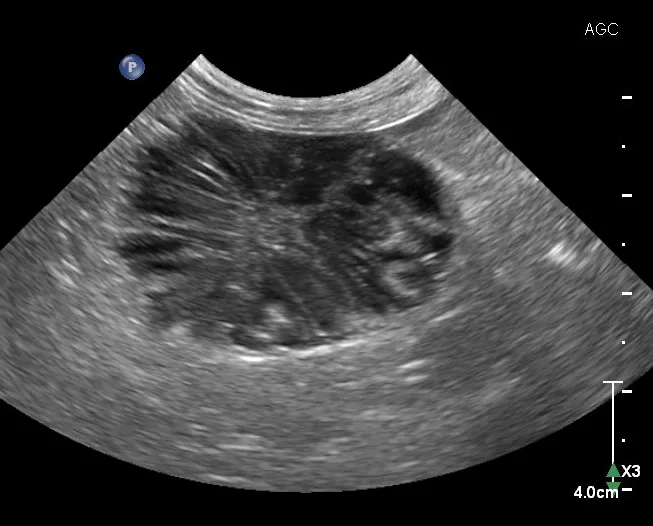

Ultrasound image of gallbladder of a dog with a hypoechoic mass containing hyperechoic radial striations.

FIGURE 5

A mature gallbladder mucocele with a central hyperechoic area that is heterogeneous with linear hyperechoic striations in a dog. This appearance is often described as a kiwifruit pattern.

Elective cholecystectomy (ie, prior to biliary obstruction or gallbladder rupture) has been shown to have a lower mortality rate than nonelective cholecystectomy (ie, after obstruction or rupture).23 Suspended (ie, not gravity-dependent) mucus and/or hyperechoic bile are both potential indications for cholecystectomy.23

Although mature gallbladder mucoceles are associated with gallbladder enlargement and wall thinning, numerous etiologies (eg, cholecystitis, gallbladder wall edema, cholecystolithiasis, cystic mucosal hyperplasia, neoplasia [rare]) can also lead to gallbladder wall thickening (>3-3.5 mm).10,20 Bile aspiration via ultrasound-guided cholecystocentesis can be performed for bile culture and/or gallbladder decompression10; however, this procedure has increased the risk for bile leakage (and secondary peritonitis) with gallbladder distension or disease of the wall.